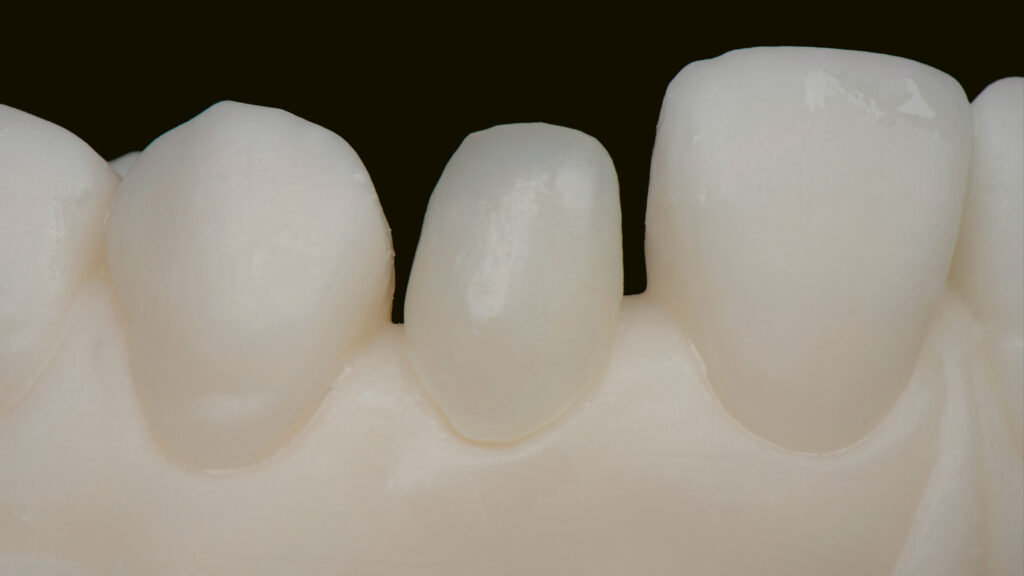

Die STL-Datei der provisorischen Implantatkrone wird automatisch erzeugt, ein TempShell (Eierschalenprovisorium) konstruiert und die STL-Datei exportiert. TempShell ist ein verschraubtes Provisorium, das noch am Tag des chirurgischen Eingriffs eingesetzt werden kann. Es wird für jeden Patienten digital erstellt und kann mit DTX Studio Suite einfach an die Implantatposition angepasst werden. Anhand des Datensatzes wird CAD/CAM-gestützt das Provisorium aus PMMA gefräst (Abb. 11). Das gefräste Provisorium (TempShell) hat zwei Flügel. Diese sorgen für die richtige Position und Stabilität im Mund (Abb. 12 und 13). Durch On-Screen-Design-Verfahren passt das Provisorium perfekt auf das gedruckte Modell und in den vorgeschliffenen Gingivaverlauf (Abb. 14).

Vita Ambria (Vita Zahnfabrik, Bad Säckingen) ist ein mit Zirkonoxid verstärktes Lithiumdisilikat mit hoher Festigkeit (>500 Mpa), das in der Presstechnik verarbeitet wird. Die Keramik eignet sich besonders für die effiziente Herstellung von hochästhetischen, langlebigen Restaurationen wie Overlays und Teilkronen. Das Presskeramik-System enthält Presspellets in den Transluzenzstufen T (transluzent) und HT (hochtransluzent) (Abb. 15). Ein Vorteil ist, dass die aus Vita Ambria gepresste Restauration vollanatomisch und monolithisch bemalt und glasiert oder mit der Verblendkeramik Vita Lumex AC (Vita Zahnfabrik) fertiggestellt werden kann. Nach dem Modellieren des hauchdünnen Käppchens (Abb. 16) und dem Pressen erfolgt das Ausbetten der Keramikschale. Die minimale Reaktionsschicht kann mit geringem Druck (2 bar) abgestrahlt werden, so dass passgenaue Ergebnisse effizient erzielt werden. Da die Schale in der Farbe A1 (HT-Rohling) gepresst wurde (Abb. 17) und die Schichtstärke nur 0,2 bis 0,3 mm beträgt, wirkt sie sehr transluzent (Abb. 18). Es folgt die Verblendung mit Vita Lumex AC. Hier zeigt sich ein weiterer Vorteil für die Umsetzung dieses Falles. Denn die Verblendkeramik kann auch auf Zirkonoxidgerüsten verwendet werden. Vita Lumex AC ist eine leutzitverstärkte Glaskeramik zur Verblendung vollkeramischer Gerüste aus Zirkondioxid-, Lithiumdisilikat- und Feldspatkeramik sowie zur Herstellung von keramischen Veneers.